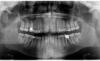

son-leta Опубликовано 1 ноября, 2013 Поделиться Опубликовано 1 ноября, 2013 Здравствуйте! Уважаемые доктора, подскажите, пожалуйста.Врач сказала, что в лечении нуждаются все 6-ки и после лечения нужно покрыть их коронками. Действительно ли нужно ставить коронки на все 4 зуба? Во время еды пища забивается внизу справа, периодически болит 26 зуб.Может быть видите что-то ещё по снимку? Спасибо. Ссылка на комментарий

Magdalena Опубликовано 1 ноября, 2013 Поделиться Опубликовано 1 ноября, 2013 (изменено) Врач права. В 16 и 36 - перелечить каналы и покрыть зубы коронками. В 46 и 26 - пульпит - пролечить каналы и покрыть зубы коронками или керамическими вкладками (определяет врач).Еще нуждается в замене пломба в 17 зубе. И на прицельном снимке я бы посмотрела 45 и 25 зубы (межзубные поверхности, по панорамному зубы "накладываются" друг на друга) Изменено 1 ноября, 2013 пользователем Magdalena Ссылка на комментарий